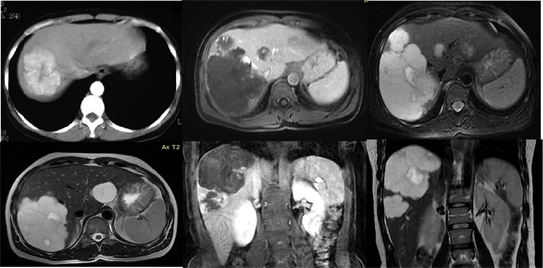

Distribution of LTP and BTTP in both genders and percentages are shown in Table 5. Our results show that overall rate of liver tumor pathologies and biliary tree tumor pathologies are same as found in literature: hemangioma [5] [16] , Figure 1; HCA, Figure 2; FNH, Figure 3; NRH, Figure 4; BC [17] , Figure 5; BCA [15] Figure 6; Cysts, Figure 7; PCLD Figure 8; Hydatid Cysts, Figure 9; HCC, Figure 10; CCA, Figure 11; Lymphoma, Figure 12; metastases, Figure 13.

Figure 1. Imaging of hepatic hemangiomas with CT and MR.

Figure 2. Imaging of hepatic adenomas with CT and MR.

Figure 3. Imaging of FNH with CT and MR.

Figure 4. Imaging of FRH with CT and MR.

Figure 5. Imaging of bilary cystadenoma with CT and MR.

Figure 6. Imaging of Biliary Cystadenocarcinoma with CT and MR.

Figure 7. Imaging of Hepatic Cysts with CT and MR.

Figure 8. Imaging of Polycytosis of the liver with CT and MR.

Figure 9. Imaging of Hydatid Cysts with CT and MR.